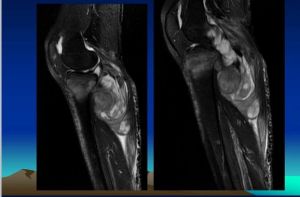

3、MRI檢查多數惡性纖維組織細胞瘤的邊界清楚,少數呈侵潤性生長,邊界不清楚,腫瘤呈結節狀,可有分葉。在T1加權像為低或中等信號,T2加權像呈高信號,注射Gd-DTPA增強後,腫瘤內不均勻強化。

患者,女,52歲,左脛骨BMFH。術前X線片及CT示脛骨斑片樣、蟲蝕狀骨破壞,周圍由硬化邊緣(略) MRI示腫瘤侵犯的範圍、軟組織包塊及周圍比鄰的關係(略)

BMFH由於缺乏特殊的影像學表現,故不能根據術前X線片、CT、MRI明確診斷,但影像學檢查可以幫助診斷,並且對確定手術方案有很大幫助。根據本組資料,作者總結BMFH影像學表現:(1)X線表現:BMFH的X線表現多種多樣,特徵性少。以蟲噬狀、斑片狀或大片狀溶骨性破壞為主,邊界不清,少數可有邊緣硬化,常伴有軟組織腫塊,骨膜反應無或輕微,這是BMFH的重要特點。(2)CT表現:更清楚地顯示骨質破壞和軟組織腫塊,骨質破壞同X線,少數病灶為囊狀或膨脹性,內有粗條索狀及格線狀嵴,並見邊緣硬化,類似良性病變,骨膜反應少見。(3)MRI表現:BMFH的MRI表現缺乏特異性,但其對腫瘤髓內侵犯、周圍邊界可清楚顯示,指導手術切除範圍,還可顯示腫瘤與鄰近血管的關係以及判斷腫瘤術後改變與術後復發等方面優於X線及CT。